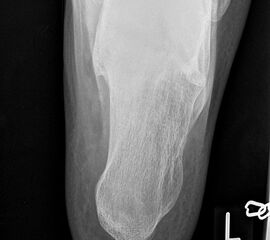

Fersenbein lateral

Positionierung:

• Patient in Seitenlage.

• Fuß mit der Außenseite aufliegend.

• Ferse liegt parallel zum Tisch.

• Röntgenröhre 90° zur Senkrechten.

• Zentralstrahl von lateral nach medial, zentriert auf das Fersenbein ca. 1-2 Querfinger distal der Malleolen.

Kennzeichen des Röntgenbildes:

• Seitliche Darstellung des Fersenbeins mit scharfen Knochenkonturen.

• Gut einsehbares unteres Sprunggelenk (Articulatio talocalcaneonaviculare).

• Gut einsehbares Gelenk zwischen Calcaneus und Os cuboideum.

Besondere Bemerkungen zum Beispielbild:

• Darstellung der Kalkaneus seitlich.

• Kleiner Traktionssporn im Insertionsbereich der Achillessehne.

• Großes Os trigonum dorsal des Talus.